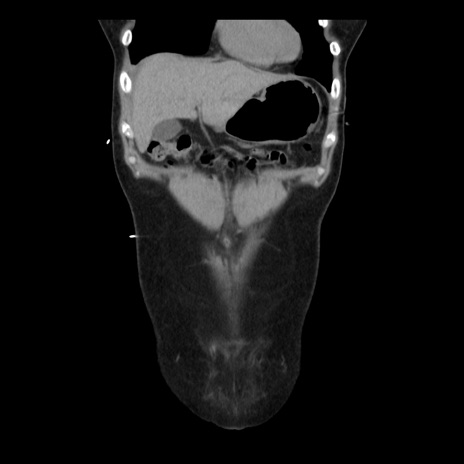

横断像